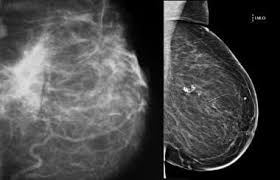

Any area that does not look like normal tissue is a possible cause for concern. For breast cancer screening purposes, the machine also creates standard 2d mammogram images. A doctor who specializes in interpreting imaging tests (radiologist) examines the images to look for abnormalities that may be breast cancer. The skin of the breast might also appear puckered, like the skin of an orange. You may have an imaging test, like a mammogram or ultrasound, for an inside look. Mammograms may show suspicious areas of the breast, white spots, and microcalcifications. There are few risks associated with mammography. Palpation of benign breast masses.

For breast cancer screening purposes, the machine also creates standard 2d mammogram images.

Mammograms are the best technique available to detect breast cancer or monitor the response of breast cancer to treatment. According to the american cancer society (acs), the most common sign of breast cancer is a new lump or mass in the breast. Finding breast lumps and seeing change in the size and shape. Rate of dcis discovery is increasing, due to screening mammograms. They're often easy to move around (mobile) and may be tender. There are two techniques for creating a mammogram. Calcifications are tiny flecks of calcium — like grains of salt — in the soft tissue of the breast that can sometimes indicate the presence of an early breast cancer. They can vary greatly from painful, hard, and immobile to soft, painless, and easily moveable. They're common on mammograms, particularly if you're postmenopausal. Breast cancer and some noncancerous (benign) breast conditions can appear white on a mammogram. Additionally, how does lump in the breast look like? Magnetic resonance imaging (mri) of the breast — or breast mri — is a test used to detect breast cancer and other abnormalities in the breast. On a mammogram, dcis usually looks like a cluster of microcalcifications.